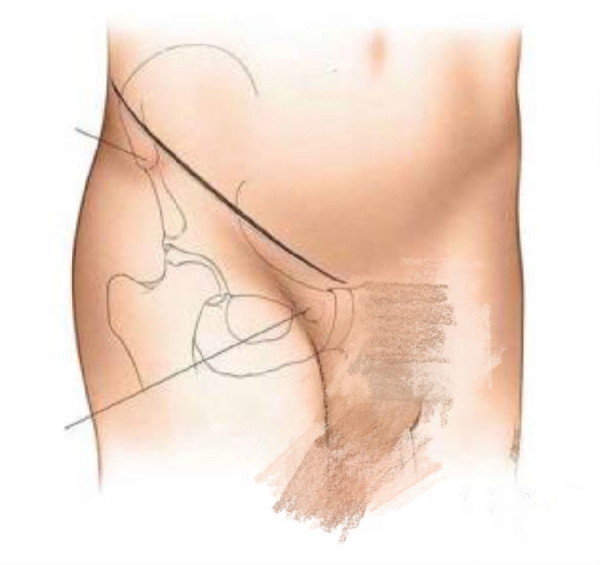

手术入路

沿纤维走行切开腹外斜肌筋膜确认并牵开髂腹股沟神经。

腹内斜肌的弓状束连同精索或子宫圆韧带牵向内侧,显露腹股沟管后壁及腹横筋膜。

触摸外侧的髂外血管并确定其位置以免损伤。

寻找腹壁下动脉,可以牵开保护也可以结扎。

切开腹横筋膜打开腹膜外间隙。

使用Deaver牵开器保护外侧的髂外血管及内侧的膀胱。

触摸骨折部位并插入长钝的挤压器,自前内侧对骨折进行挤压复位。

这种复位操作可以将移位的前柱向后推,也可以把后柱的内侧面连同四方平面推向外侧并纠正其旋转,以此来复位骨折。

纵向及侧方牵引髋关节可以方便复位。继续保持剥离器的挤压复位的同时打入螺钉,注意防止挤压器滑脱伤及前方的髂外血管及后方的闭孔血管神经。